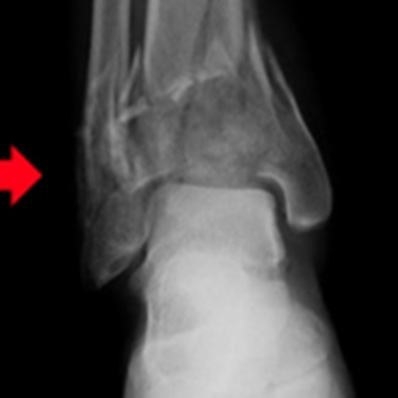

Pylon骨折

踵骨骨折